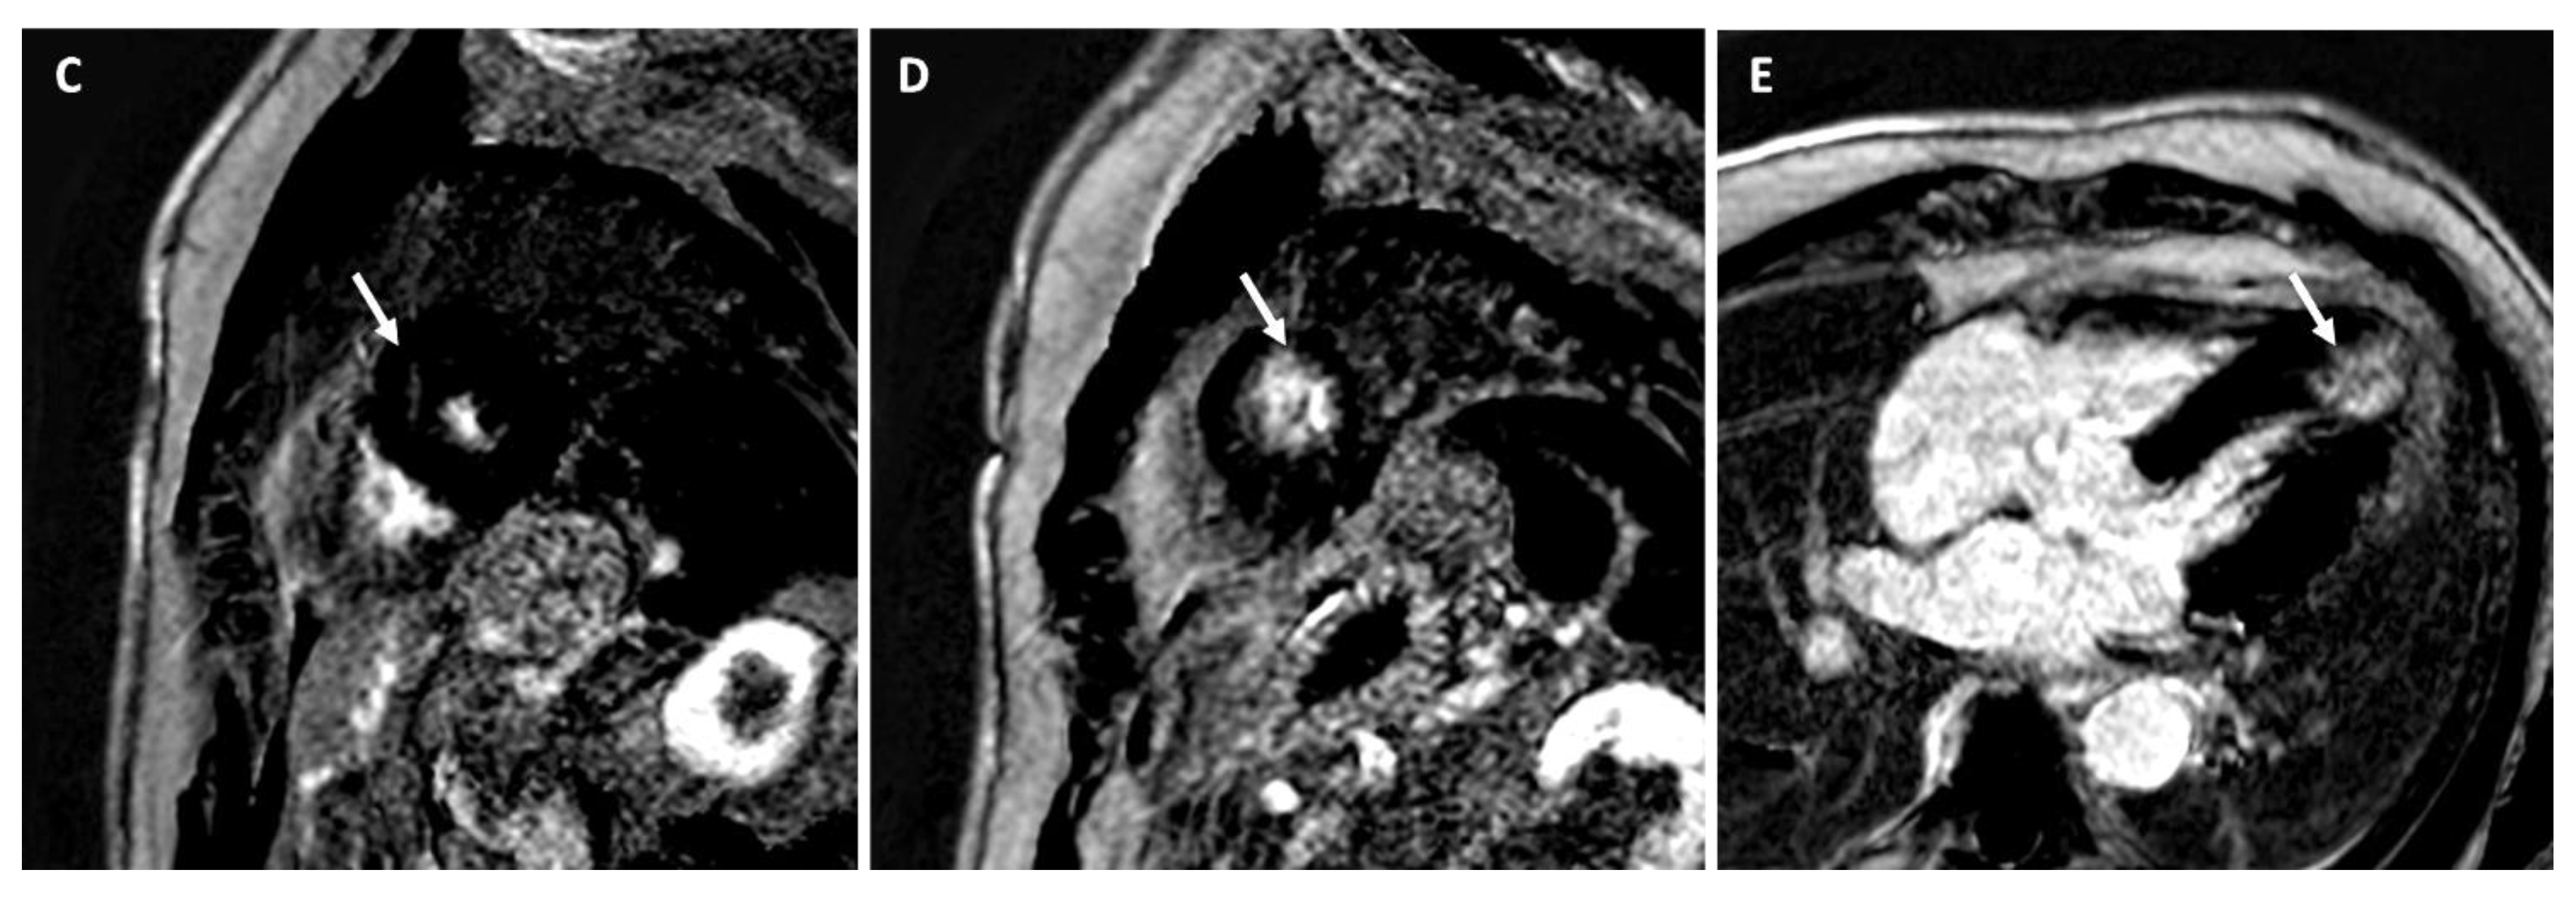

Left Dominant Arrhythmogenic Cardiomyopathy (LDAC)

- Palumbo, P.; Cannizzaro, E.; Di Cesare, A.; Bruno, F.; Schicchi, N.; Giovagnoni, A.; Splendiani, A.; Barile, A.; Masciocchi, C.; Di Cesare, E. Cardiac magnetic resonance in arrhythmogenic cardiomyopathies. Radiol. Med. 2020, 125, 1087–1101. [Google Scholar] [CrossRef]

| LGE/LIE | |||||||

| Type | Linear | Patchy or massive | Linear | Linear | Linear | Linear | Linear or parchy |

| Layer | Mesocardial | Mesocardial | Mesocardial | Mesocardial | Subepicardial Mesocardial | Subepicardial | Subendocardial Mesocardial |

| Site | Interventricular juctions | Hypertrophic area; interventricular junctions | Septum; infero-lateral LV wall | Variable, not associated with NC area | Anterior RV wall | Infero-lateral LV wall | Circumferential; septum; lateral LV wall |